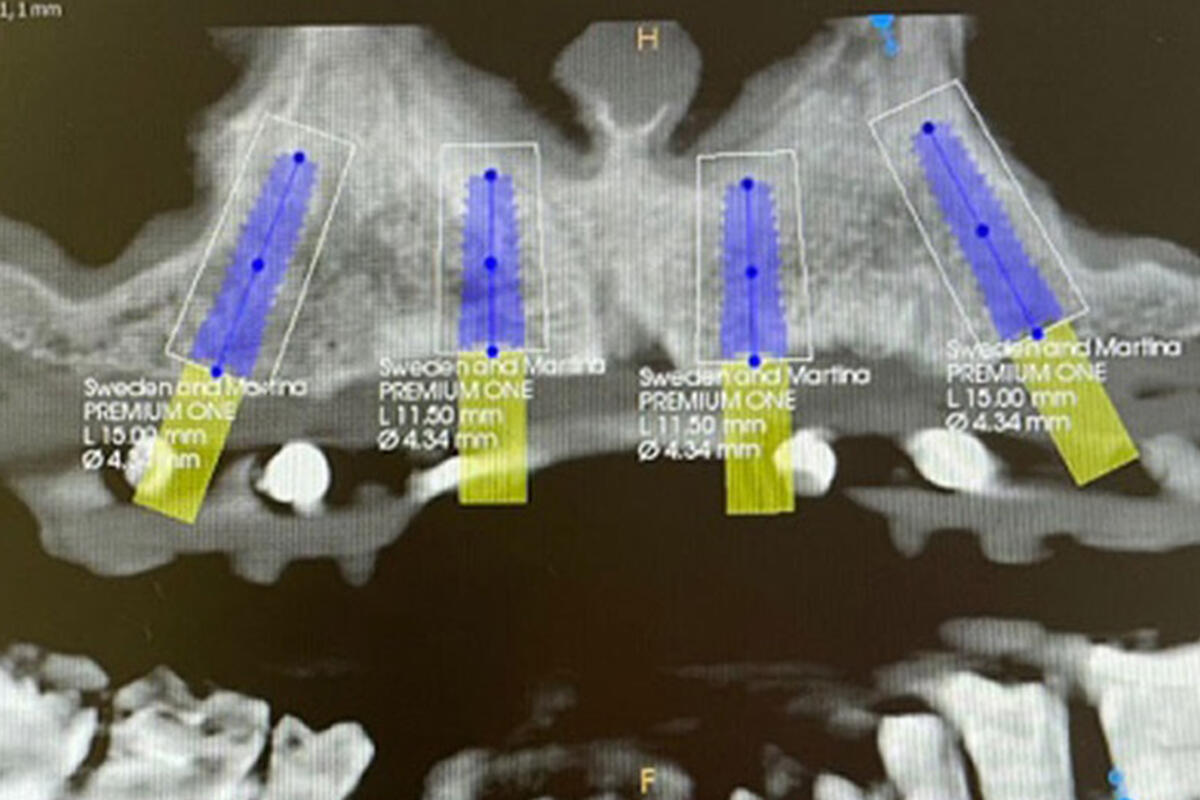

La tecnologia digitale cambia, in meglio, il lavoro del dentista